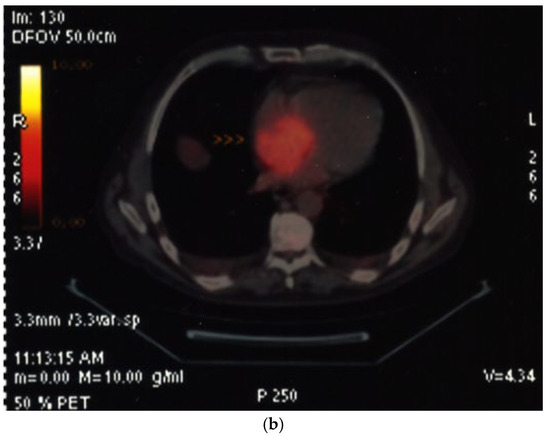

| Viability in chronic CAD |

| No reflow in acute MI |

| Cardiac tumors |

| Assessment of myocardial ischemia/viability during stress echocardiography |

| Imaging method | Low-MI-contrast-specific imaging—Flash–Replenishment |

| Imaging planes | standard apical views additional modified views to optimize perfusion imaging in basal anterior/lateral segments or views to optimize the display of suspected tumors |

| Contrast application | Infusion bolus injection acceptable for demonstration of vascularization of a cardiac tumor |

| Typical findings | Normal myocardial perfusion: homogeneous opacification of the segment, contrast replenishment within 5 s after flash (2 s during stress) Abnormal perfusion: delayed contrast replenishment, perfusion defect, often combined with abnormal wall motion Tumors may show patchy opacification and include dark areas due to necrosis |

| Alternative imaging | Doppler velocity measurements (see above), nuclear imaging (SPECT, PET), cardiac MRI for assessment of myocardial perfusion and viability Tumors: MRI provides tissue characterization and should be performed unless there is typical myxoma (attached to the interatrial septum) |